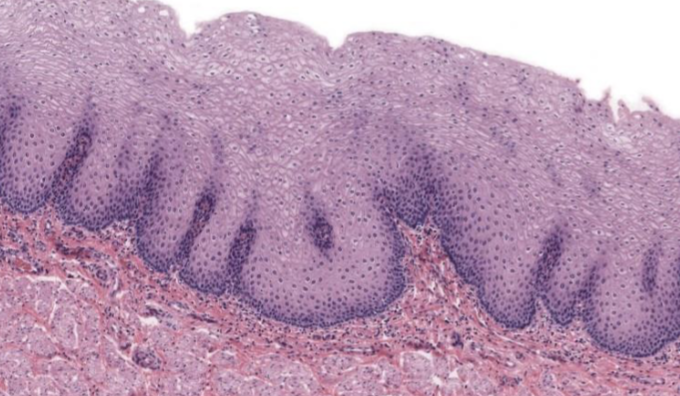

Clasifique tejido epitelial

estratificado queratinizado

Indique sitio anatómico donde se encuentra

piel delgada

Forma de sus células

plano

Número de capas

estratificado

Indique función

protección